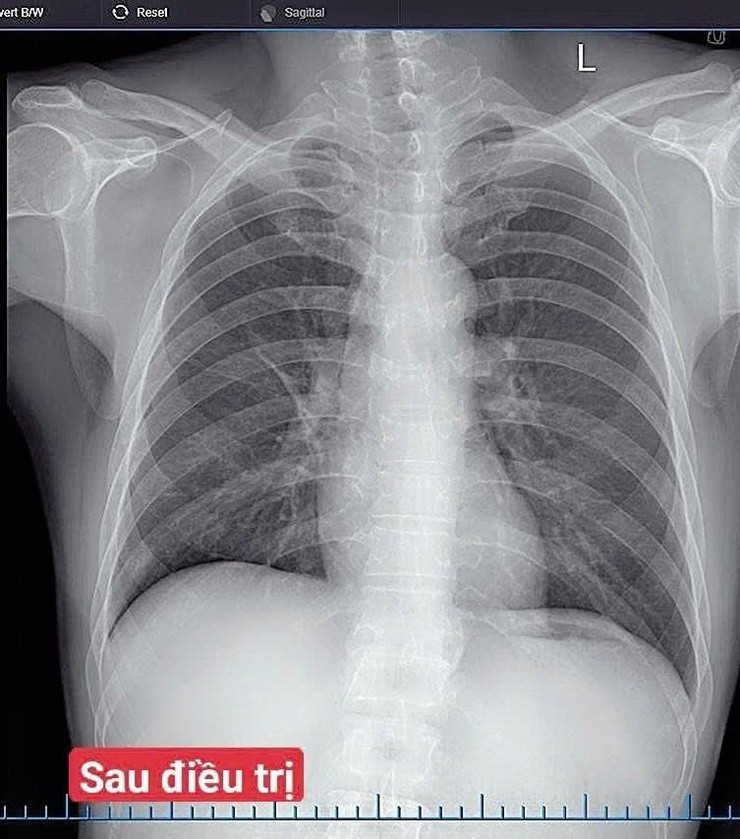

Hình ảnh sau điều trị của người bệnh. Ảnh BV

Sau 7 ngày điều trị, tình trạng bệnh nhân cải thiện rõ rệt: Hết sốt, giảm ho, giảm đau ngực, ăn ngủ tốt, chỉ số sinh tồn ổn định.